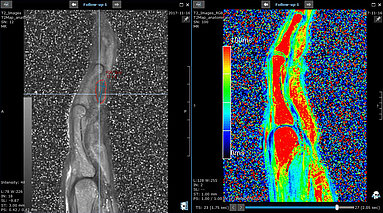

Modern technology advancements, specifically in the area of medical imaging, have substantially improved the evaluation of therapy response and the ability to monitor disease status post-treatment in…